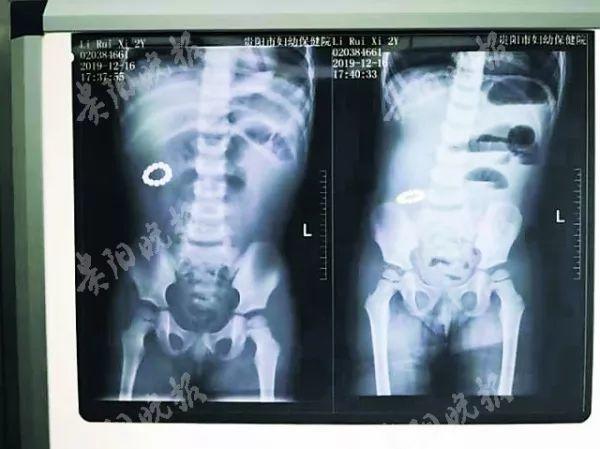

【两岁儿童误吞13颗磁力*珠钢**,13颗磁力*珠钢**黏附在孩子肠壁聚集成环状,导致肠道10处缺血坏死穿孔】